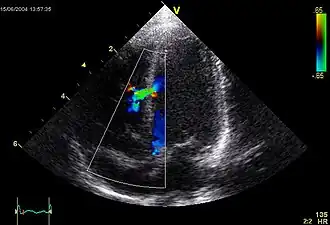

![]() Imagen ecocardiográfica de una comunicación interventricular moderada en la parte media muscular del septo interventricular. El trazado en la parte inferior izquierda muestra el flujo durante un ciclo cardíaco completo y la marca roja el momento del ciclo cardíaco en el que la imagen fue capturada. Los colores representan la velocidad del flujo sanguíneo. El flujo va desde el ventrículo derecho al ventrículo izquierdo (a la izquierda de la imagen). El tamaño y la posición es típica de una CIV en el período neonatal. | ||

La comunicación interventricular (CIV) es la cardiopatía congénita[1] más frecuente, caracterizada por el cierre incompleto del tabique interventricular—la pared que divide los dos ventrículos del corazón—lo que permite la comunicación libre entre ambos ventrículos. Con frecuencia se asocia a otros defectos estructurales, como la tetralogía de Fallot y el síndrome de Down.[2] Algunos estudios han mostrado que la CIV tiene una prevalencia entre el 2-5% de los nacimientos y que en el 80-90% de los casos se cierra poco después del nacimiento.[3][4] La comunicación interventricular puede también formarse pocos días después de un infarto de miocardio[5] (ataque al corazón) por el desgarre mecánico de la pared interventricular antes de que se forme la cicatriz característica de la enfermedad durante la remodelación del tejido muerto por macrófagos.

- CIV muscular: el defecto se encuentra en la porción inferior muscular del tabique. Las CIV apicales pertenecen a este grupo. Se presenta en hasta el 20 por ciento de todos los casos de CIV.[1]